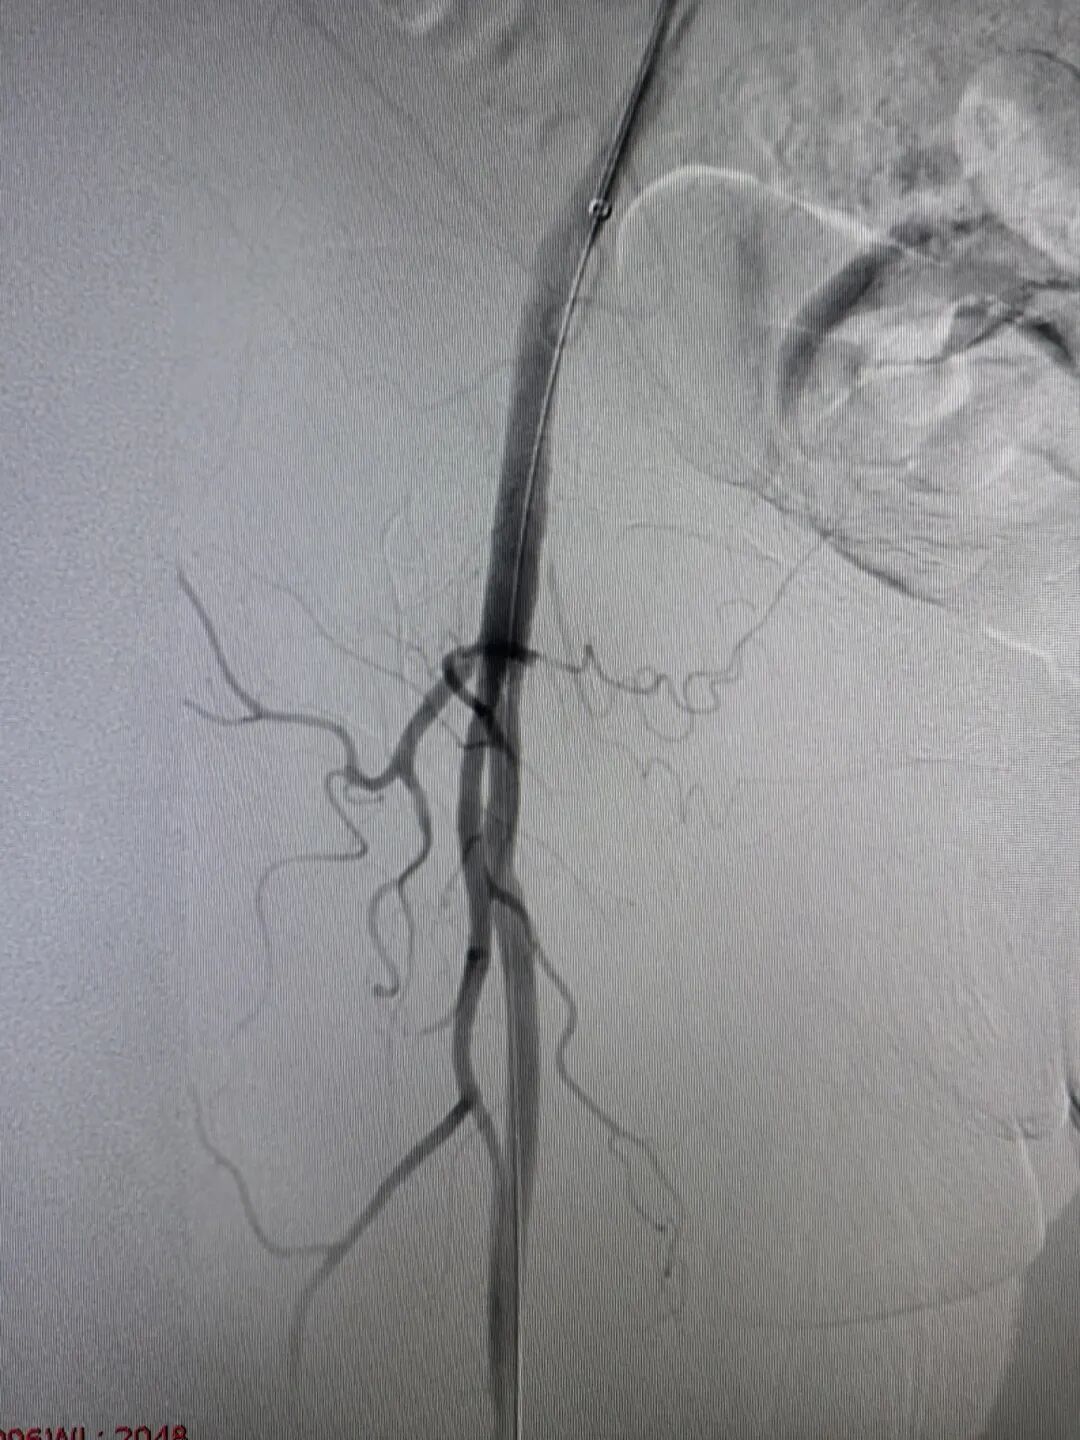

(介入术后闭塞的血管完全再通)

两个小时后,手术顺利完成。孙奶奶右下肢的皮温、皮色即刻改善,足背动脉搏动恢复,疼痛麻木消失。从入院到血运重建,全程高效顺畅,没有浪费一分一秒。